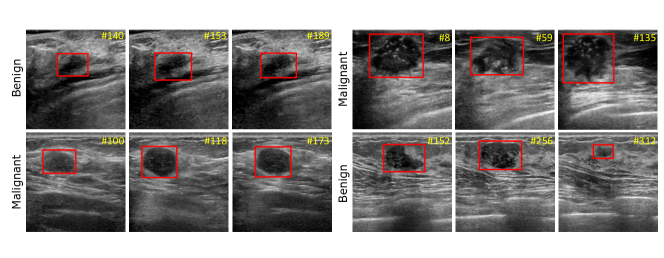

Refer to caption

Figure 1: Examples of our annotated ultrasound video dataset for breast lesion detection.

To do so, we in this work first provide a video dataset for breast lesion detection in ultrasound; see Fig. 1 for several examples of annotated videos. Then, we present a novel network for boosting breast lesion detection in ultrasound videos by aggregating video-level classification features and clip-level temporal features, which contains a local temporal feature from the input video frames and a global temporal information from shuffled video frames. The contributions of this work could be summarised as: 1) We develop a novel network to learn clip-level temporal features and video-level lesion classification features for boosting breast lesion detection in ultrasound videos. 2) We collect and annotate a video dataset (118 videos) for breast lesion detection in ultrasound videos. 3) An inter-video fusion module is devised to attentively aggregate local features from the original video frames and global features from the shuffled video frames, while an intra-video fusion module is developed to fuse temporal features encoded among adjacent video frames. 4) Experimental results on our annotated dataset demonstrate that our network sets a new state-of-the-art performance on breast lesion detection in ultrasound videos.